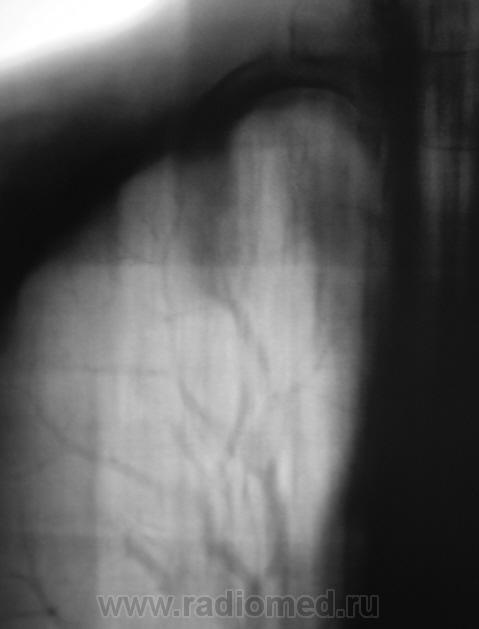

Взяли на контроль.  Какие мнения будут по поводу наличия/отсутствия специфического процесса.

Произвели стандартное дообследование.